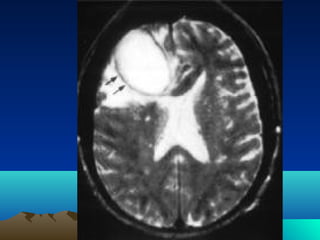

•CT scan

•MRI